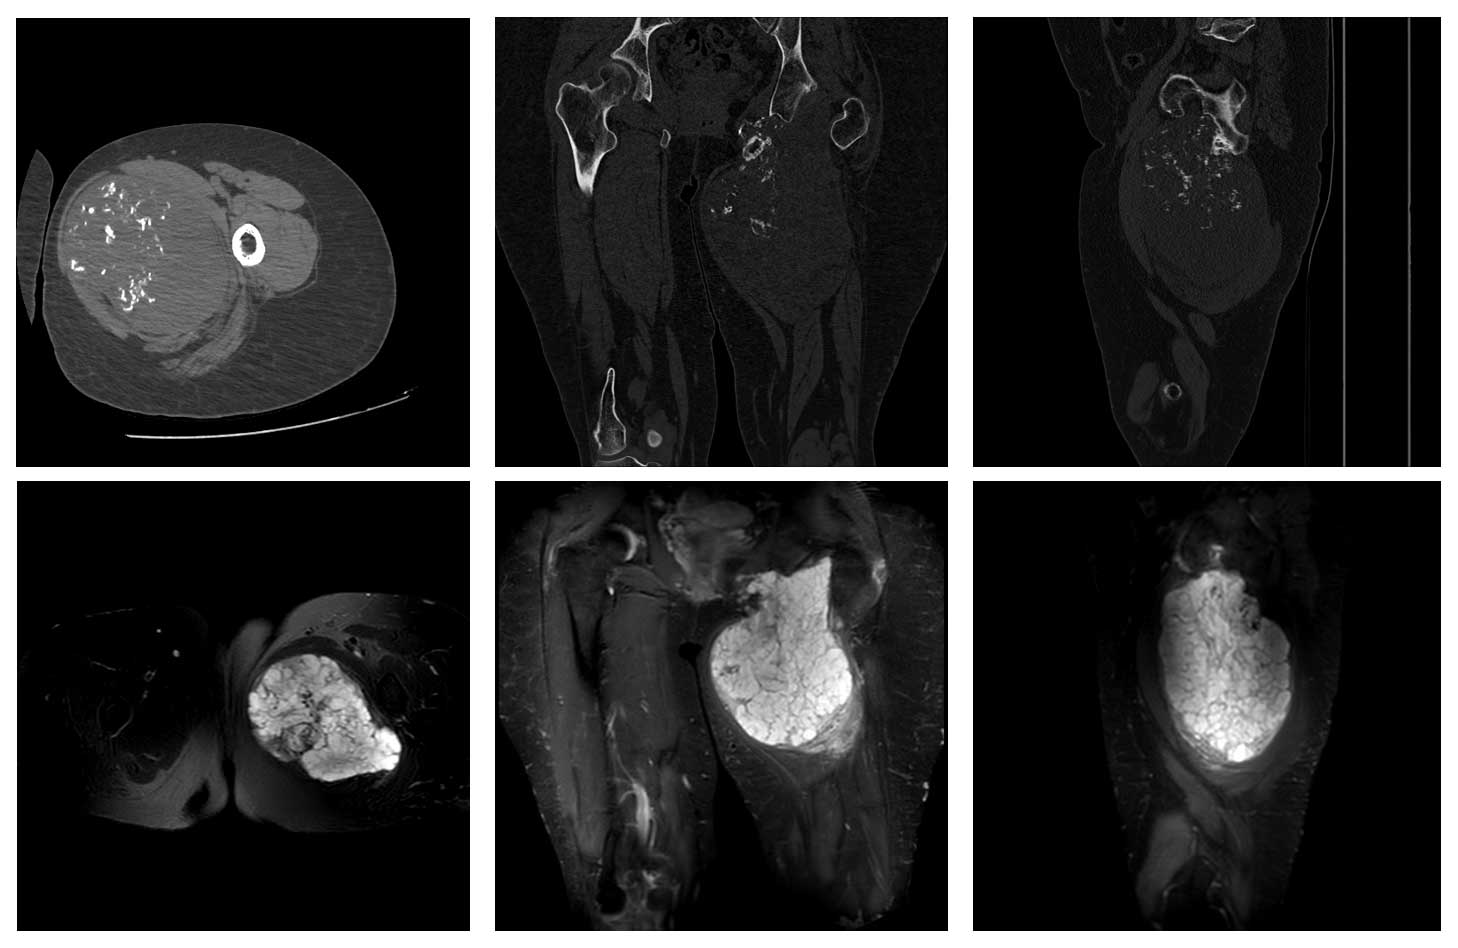

Ameliyat Öncesi: Tomografi ve MR’da pubik kol ve asetabulum inferior kaynaklı düzensiz sınırlı kalsifikasyon içeren büyük boyutlu kitle dokusu görülmekte.